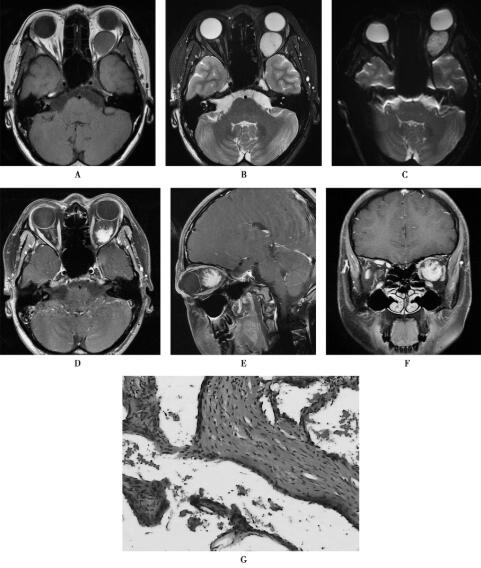

图1左眼眶海绵状血管瘤

1.眼眶海绵状血管瘤球后有类圆形肿块影,信号均匀,T1WI低信号、T2WI和DWI呈高信号,增强扫描肿块表现为“渐进性强化”,邻近眼外肌和视神经受压移位,眶尖和眶周骨质未见异常改变。

左眼眶海绵状血管瘤。HE染色(×40倍),镜下可见排列紊乱的大小不一的血管团(图1G)。

眼眶海绵状血管瘤是成人眶内最常见良性肿瘤,好发于青中年女性,常单侧发病,生长缓慢,视力一般不受影响。渐进性轴性眼球突出是常见临床表现。海绵状血管瘤由大小不等血管腔构成,内部血液流动缓慢。本肿瘤在T1W I上呈等或略低信号,T2W I上呈高信号。多回波脉冲序列上伴随TE值升高,海绵状血管瘤的信号强度亦升高,此征象和增强扫描病灶渐进性强化为血管瘤的特征性改变,据此MRI可作出眼眶海绵状血管瘤的定位和定性诊断。本病一般不累及眶尖,故眶尖正常脂肪仍然存在。